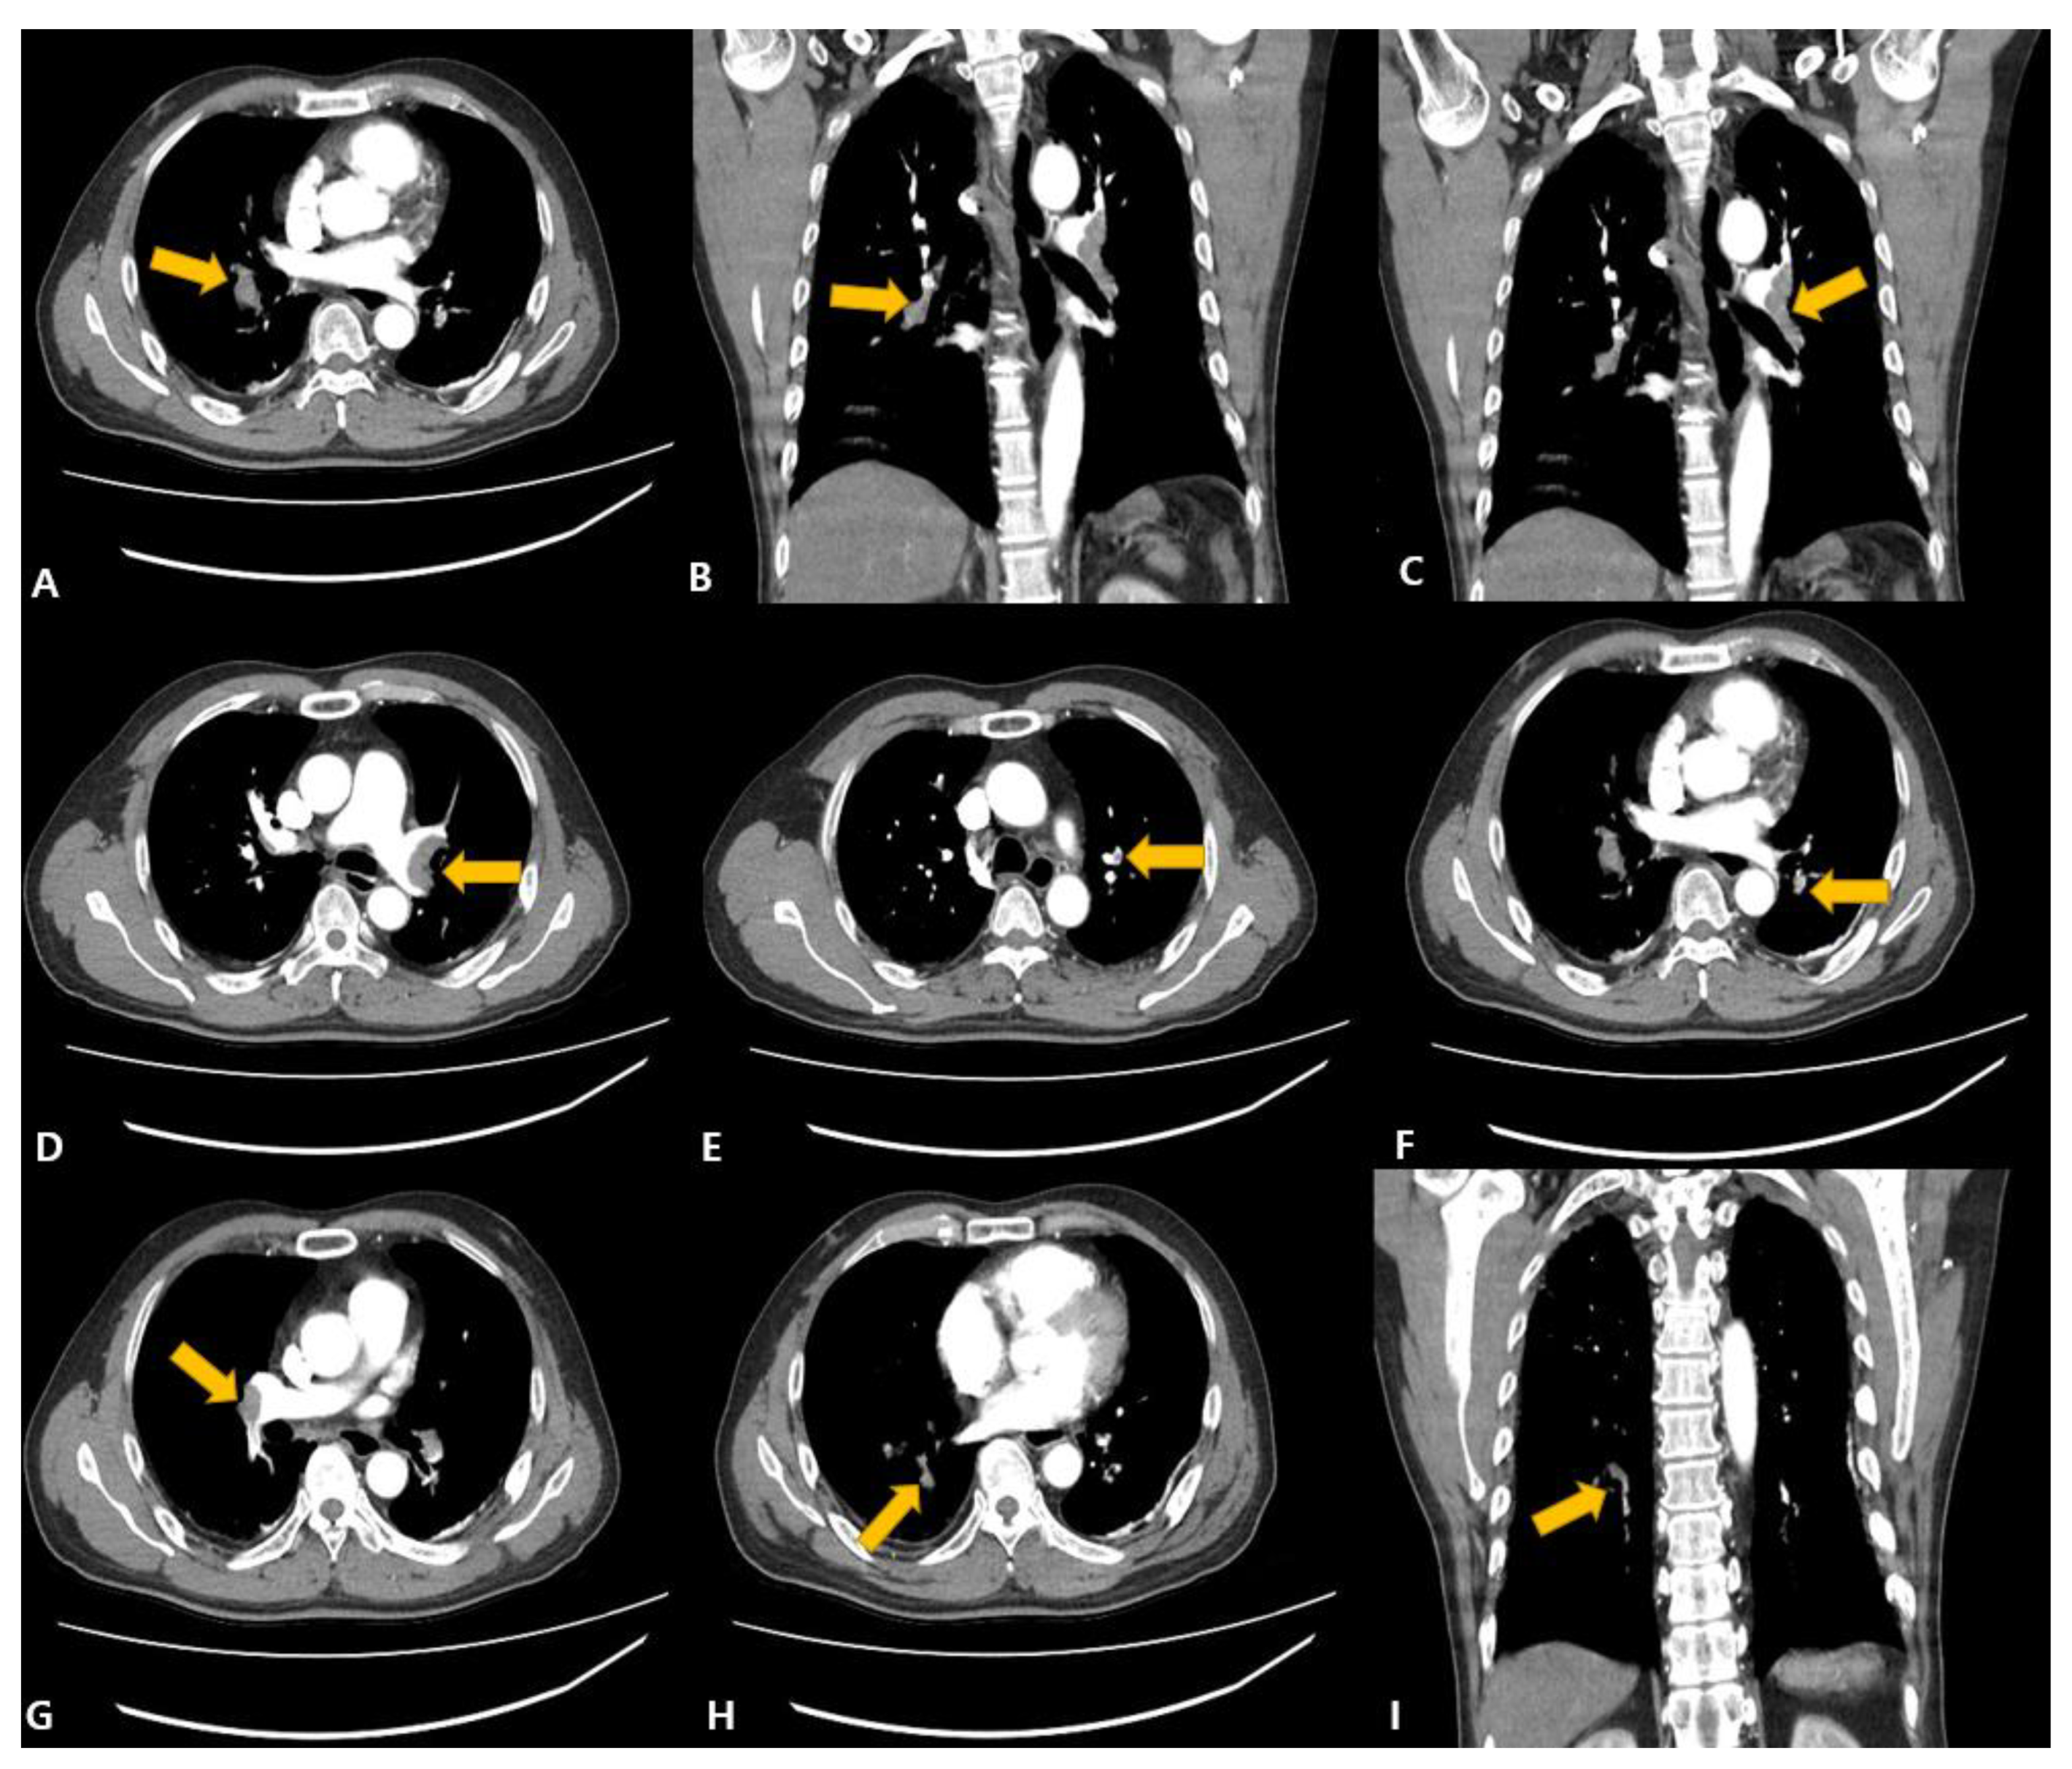

2. Case Presentation